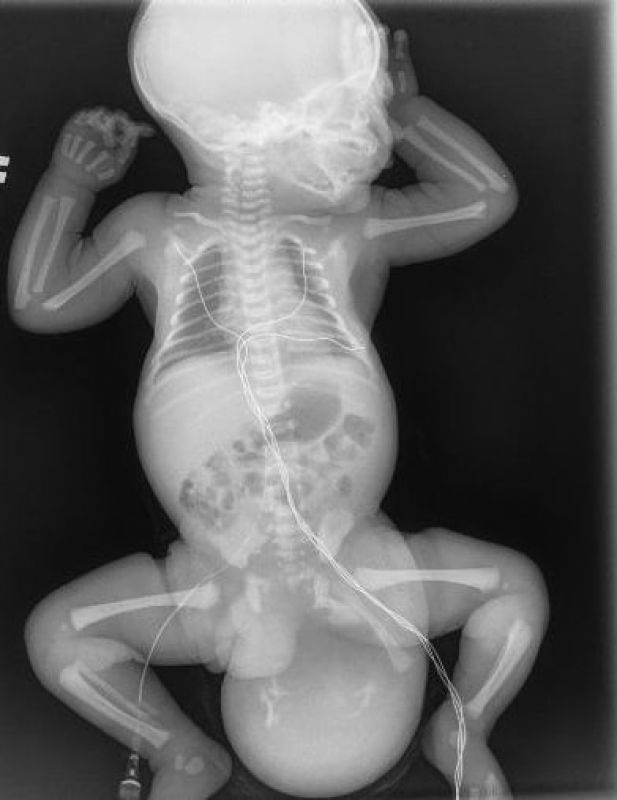

Изначально в больницу поступила женщина на 38-й неделе беременности. На обследовании обнаружилось, что у плода есть врождённый порок — крестцово-копчиковая тератома. Это опухоль с неоднородной структурой. В итоге женщине провели кесарево сечение.

Мальчик появился на свет весом 3 230 граммов и ростом 50 сантиметров. А вес опухоли на теле малыша составил порядка 650 граммов.

Опухоль, которую вырезали младенцу. Фото: Министерство здравоохранения Московской области

Как выяснилось после операции, опухоль была доброкачественной, однако в ней содержались элементы кишечной трубки, ткани поджелудочной железы, фрагменты костной и хрящевой тканей, а также клетки волос и ногтей.